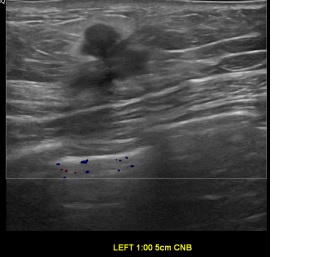

상기환자는 만져지는 멍울로 내원하신 60대초반

여성분으로 의심스러운 좌측혹 조직검사 시행해 으로 유방암 진단되었습니다